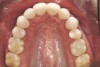

Figure 4a  Corticotomy SFOT. A 42-year-old male presented with a history of extraction orthodontic therapy (A). Incisors were too upright and had severe incisal wear. He was concerned about esthetics of the worn teeth and his insufficient lip support.

Figure 4a